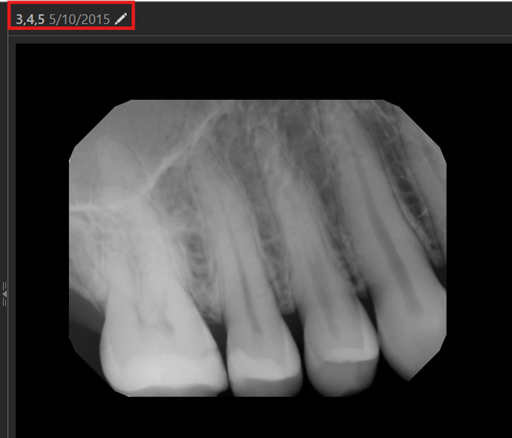

Increased Font Size of Date

For visual consistency and improved readability, in the header that displays the teeth and date for an image, the font size of the date is now the same as that of teeth.